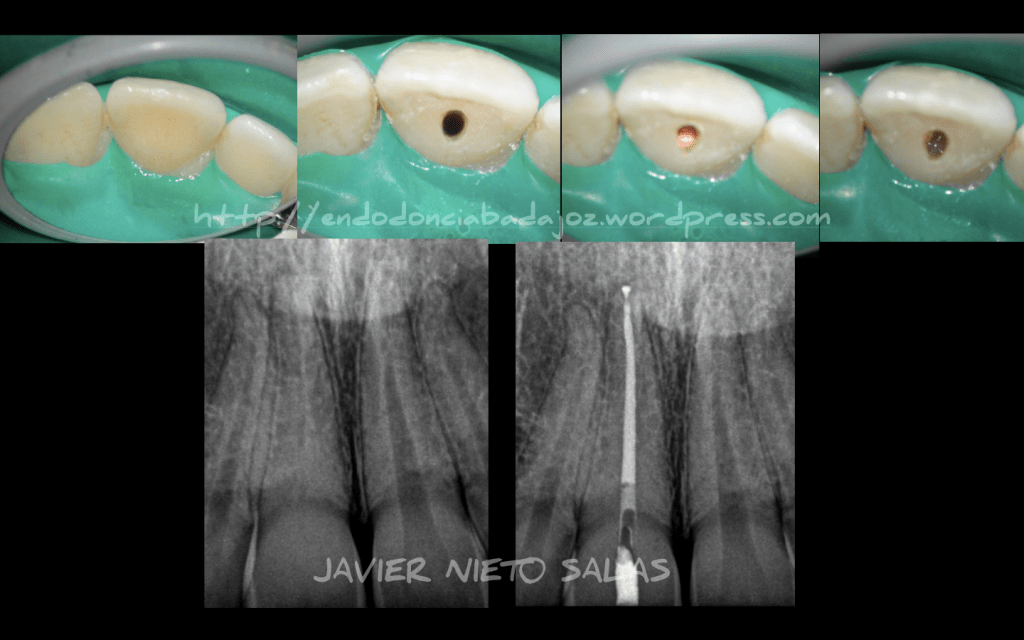

Y por último, y dejando a un lado, todas estas cosas que me apetecía poner en nuestro blog, subo un casito, no muy complicado, de un premolar inferior con 3 conductos. La magnificación hace que sea mucho más sencillo.

Hola a tod@s!!!! Necrosis Pulpar con periodontitis apical asintomática. Tratamiento en una sola sesión de 90 min de trabajo, con más de 20 min dedicado a la irrigación tras la instrumentación. Se sospechaba de Fractura Vertical , pero no observamos ninguna línea de fisura. Se obturó con condensación Vertical con Ola continua y un backfilling con gutapercha inyectada. Dos años después, se observa un resultado satisfactorio. Feliz Verano!!!!